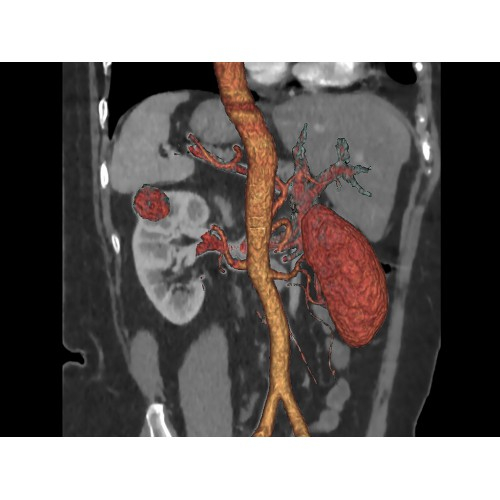

Современный КТ аппарат GE Optima CT520 – это инновационное оборудование для точной и быстрой диагностики. Он сочетает в себе передовые технологии, надежность и удобство использования, что делает его востребованным в медицинских учреждениях различного профиля.

• Высокое качество изображения благодаря усовершенствованной системе реконструкции данных.

• Широкая область применения: от неврологии до кардиологии и онкологии.

КТ аппарат GE Optima CT520 используется для диагностики широкого спектра заболеваний:

• Неинвазивная оценка состояния коронарных артерий.

• Диагностика атеросклероза и других сердечно-сосудистых патологий.

Онкология

• Раннее выявление новообразований и контроль эффективности лечения.